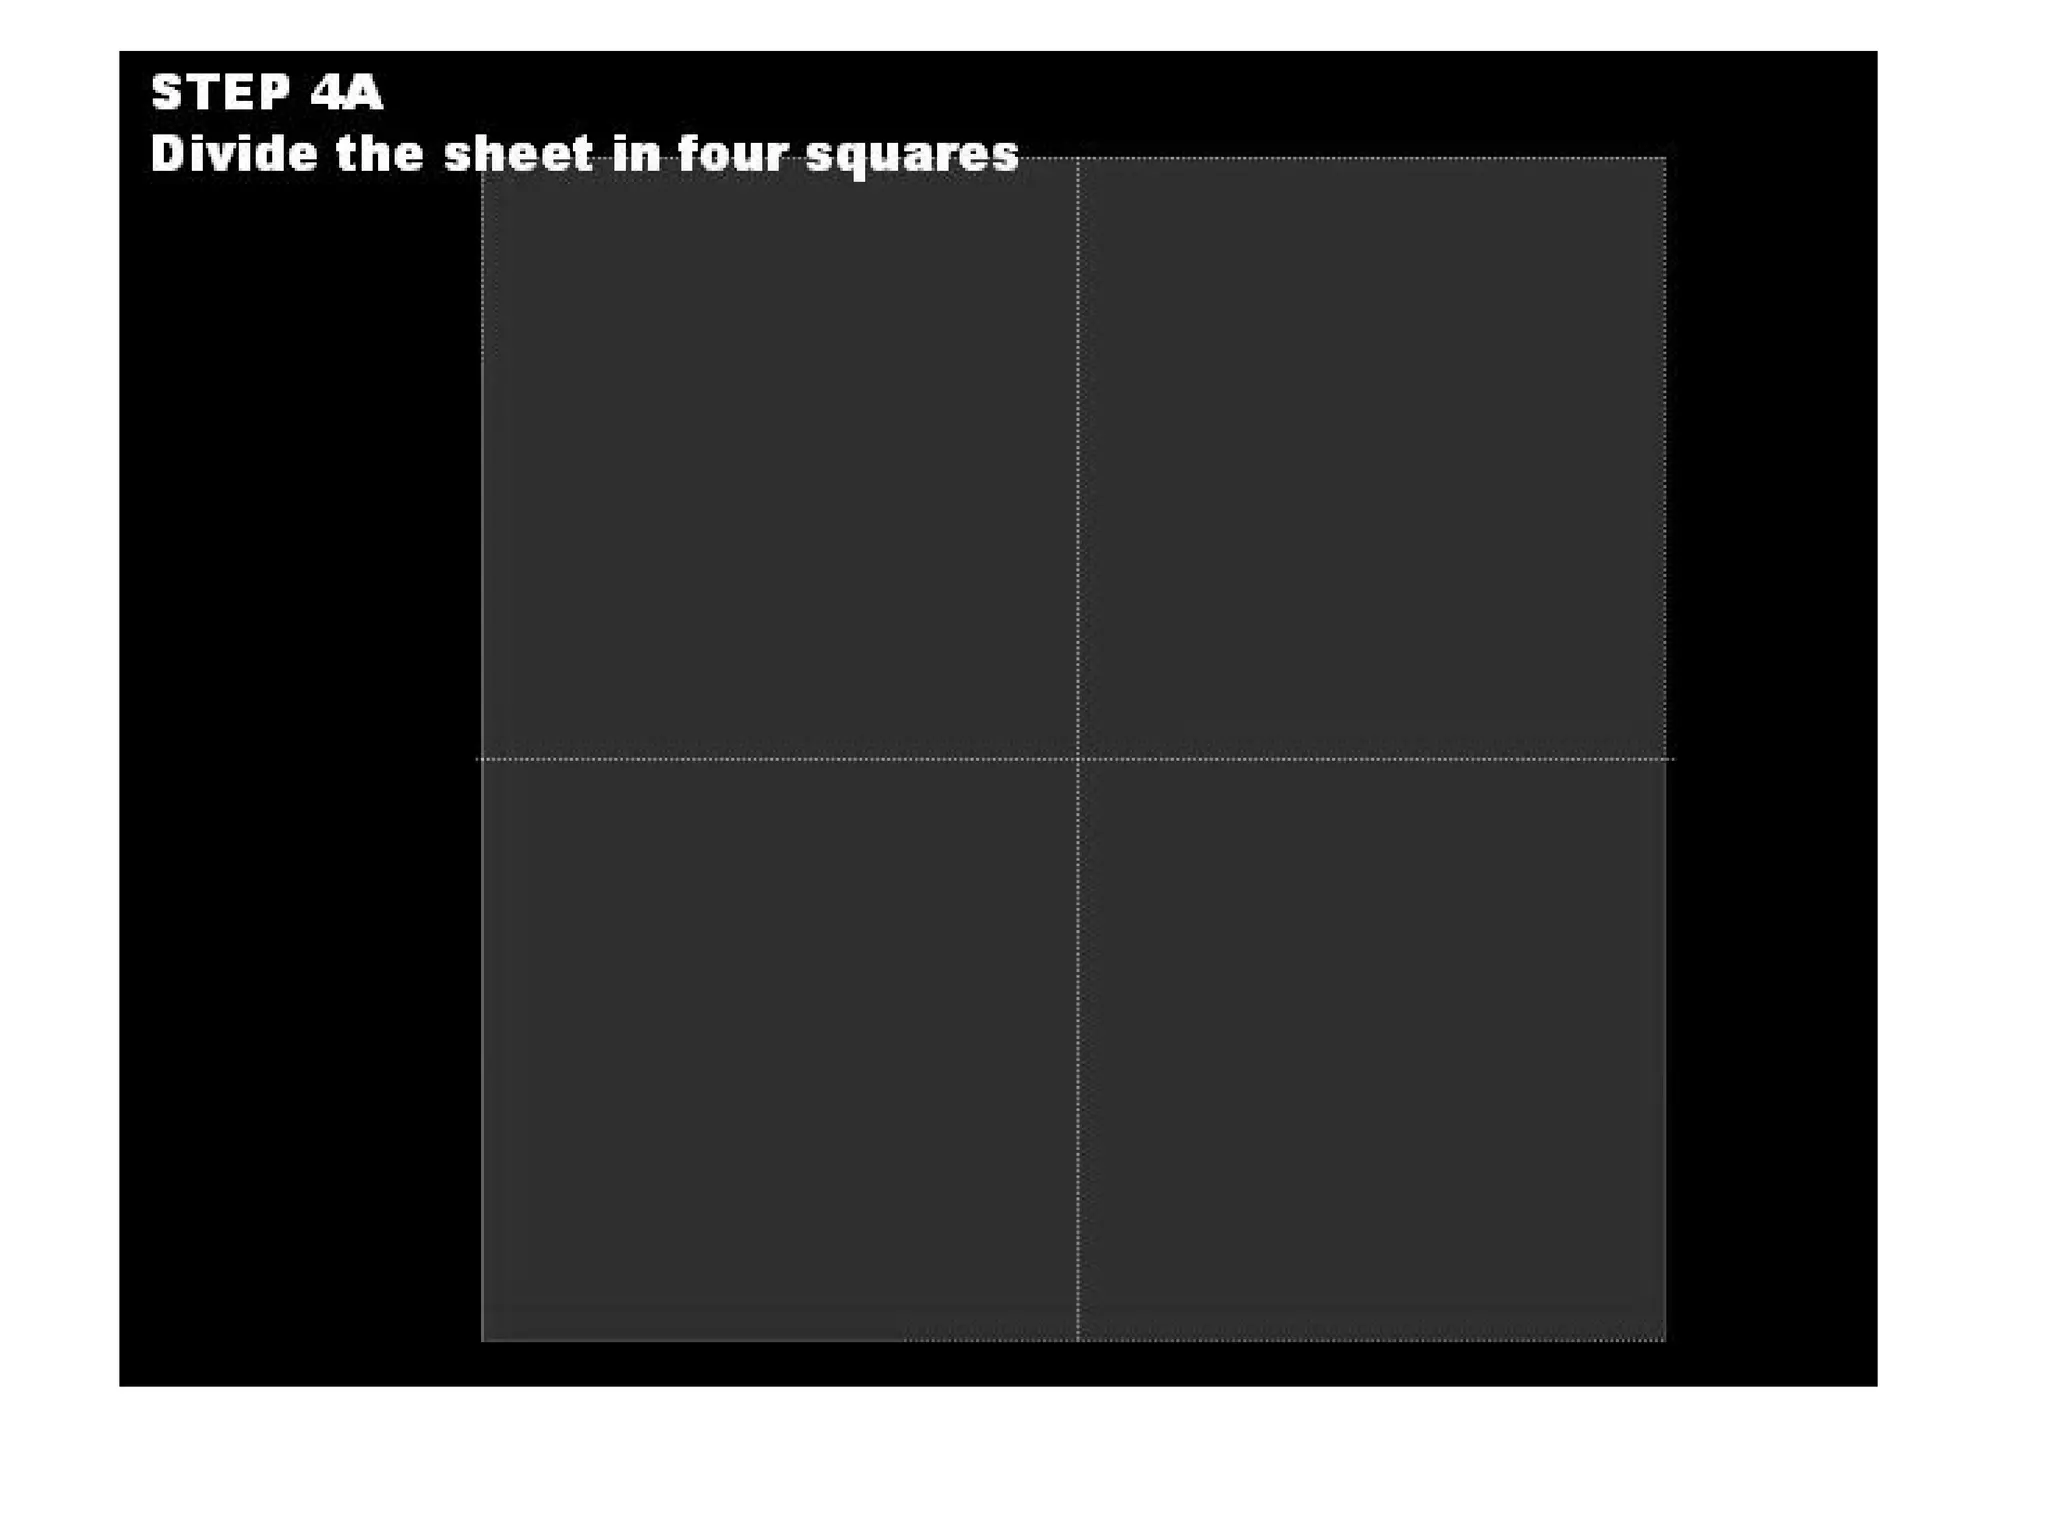

This document discusses the materials and components used for rubber dam isolation in dentistry. It describes the different types of rubber dam materials including color options and napkins to absorb moisture. It also outlines the tools needed such as punches to make holes, templates and stamps to guide hole placement, clamps to secure the dam, and other accessories like wedges and lubricant. Finally, it provides guidance on punching holes for different types of teeth and properly placing clamps in the rubber dam.